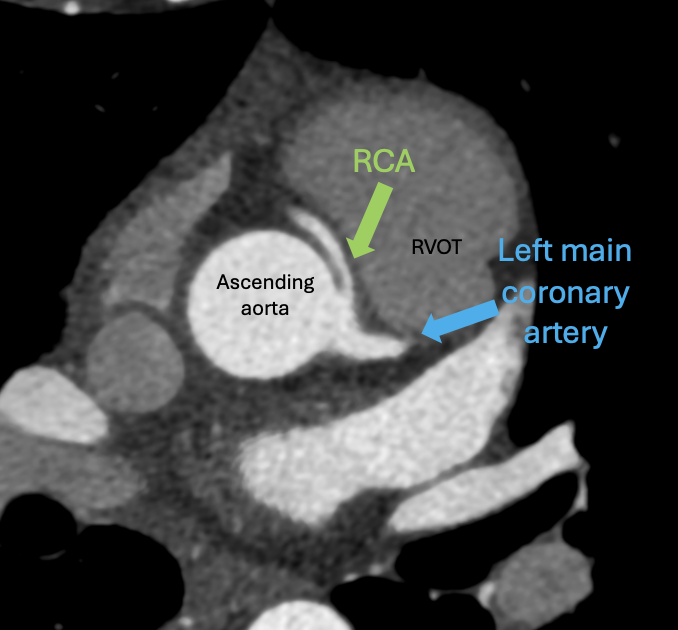

🫀 Anomalous origin of the RCA from the left coronary sinus 📍 Not all coronary anomalies are "malignant"—but all deserve careful evaluation. 💡 Pearl: If you can’t find the RCA where it “should” be, expand the search! #Cardiology #Radiology #Radres #Medtwitter

👀Coronary artery anomalies! One image. Everybody knows the rules. Which one is shown here? 🫀👇 #Radiology #Cardiology #Medtwitter #Radres